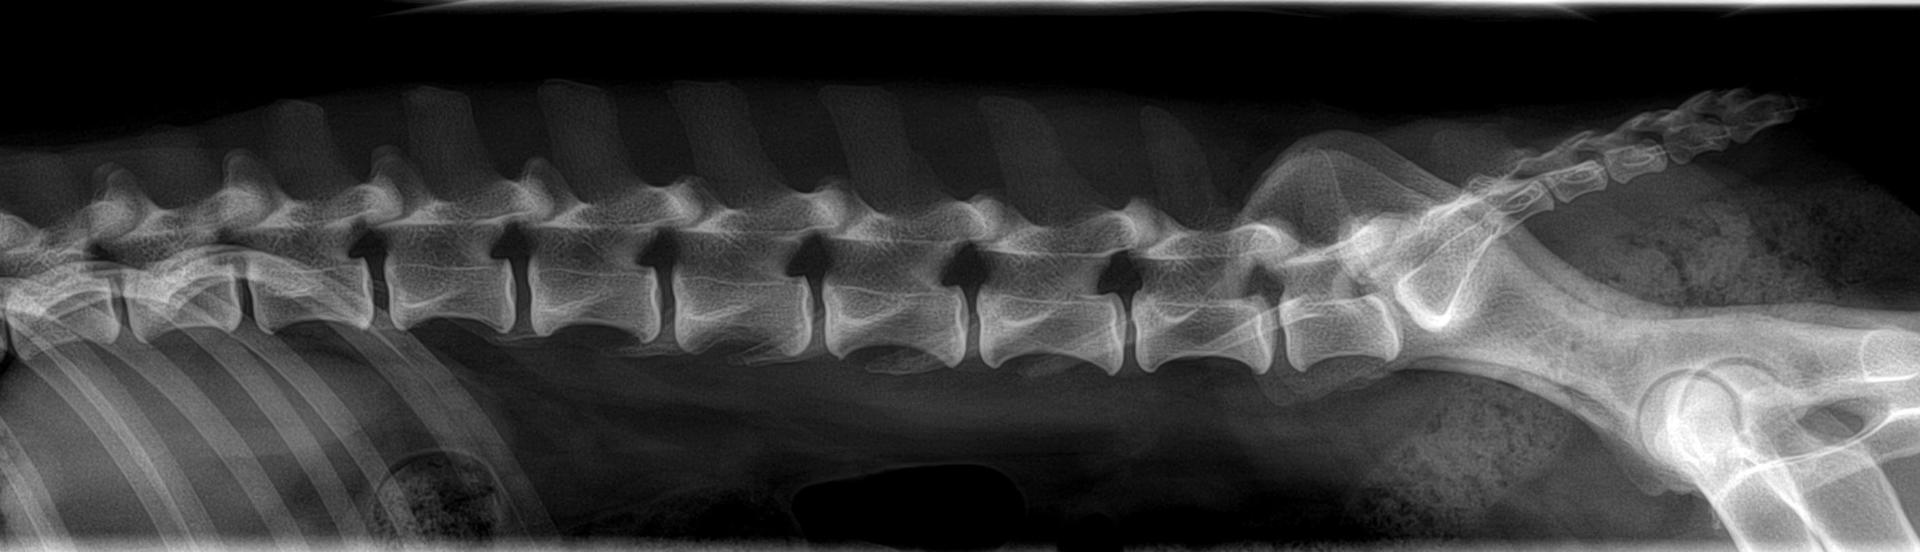

- Breites chirurgisches Spektrum innerhalb der Weichteilchirurgie, der orthopädischen Chirurgie, Neurochirurgie, Thoraxchirurgie u.a. chirurgische Fachgebiete